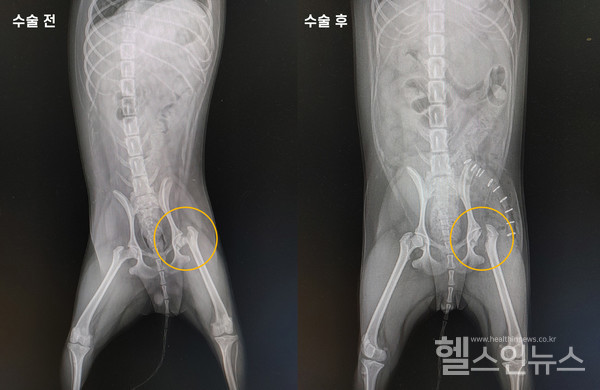

반려동물 보행 이상으로 동물병원에 내원하면 촉진 및 방사선촬영을 진행한다. 대퇴골두허혈성괴사가 있는 아이들은 앞서 말한 것처럼 대퇴골두가 울퉁불퉁한 모양이다. 진통제나 레이저 치료 등을 통한 내과적 치료도 가능하지만 근본적인 원인을 치료하는 대퇴골두제거수술(FHNO, Femoral Head & Neck Ostectomy)을 권한다. 대퇴골두제거수술은 말 그대로 대퇴골두를 제거해 주는 수술이다. 대퇴골두 없이 아이가 어떻게 보행할 것인지에 대한 의문이 생길 수 있다. 하지만 걱정하지 않아도 된다. 제거된 대퇴골두 주변의 근육과 섬유조직이 대퇴골두의 역할을 하기 때문이다. 수술 후 관리도 매우 중요하다. 충분한 재활을 통해 근육이 충분히 회복할 수 있도록 해야 하며 과격한 놀이나 운동은 삼가는 것이 좋다.